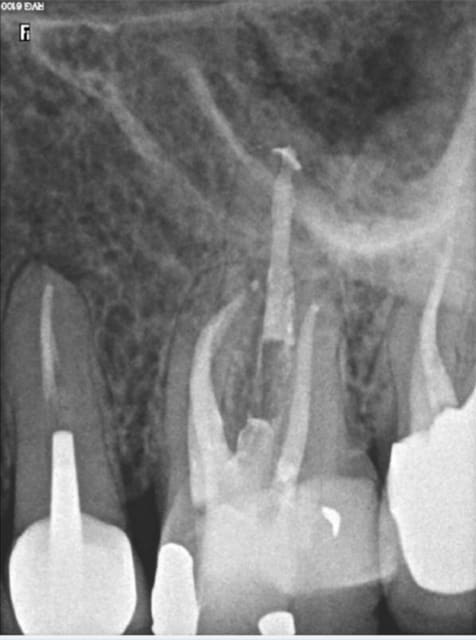

11/04/2016 à 19h57

1.Essayage du cone.

2.scellement du cone.

3. cone coupé au friendo.

4. léger down pack + foulé au machtou.

5. Chute du cone dans le canal.

6. thermo compaction au mac spadden.

Capture d e cran 2016 04 11 17.51 - Eugenol

Capture d e cran 2016 04 11 17.52 - Eugenol